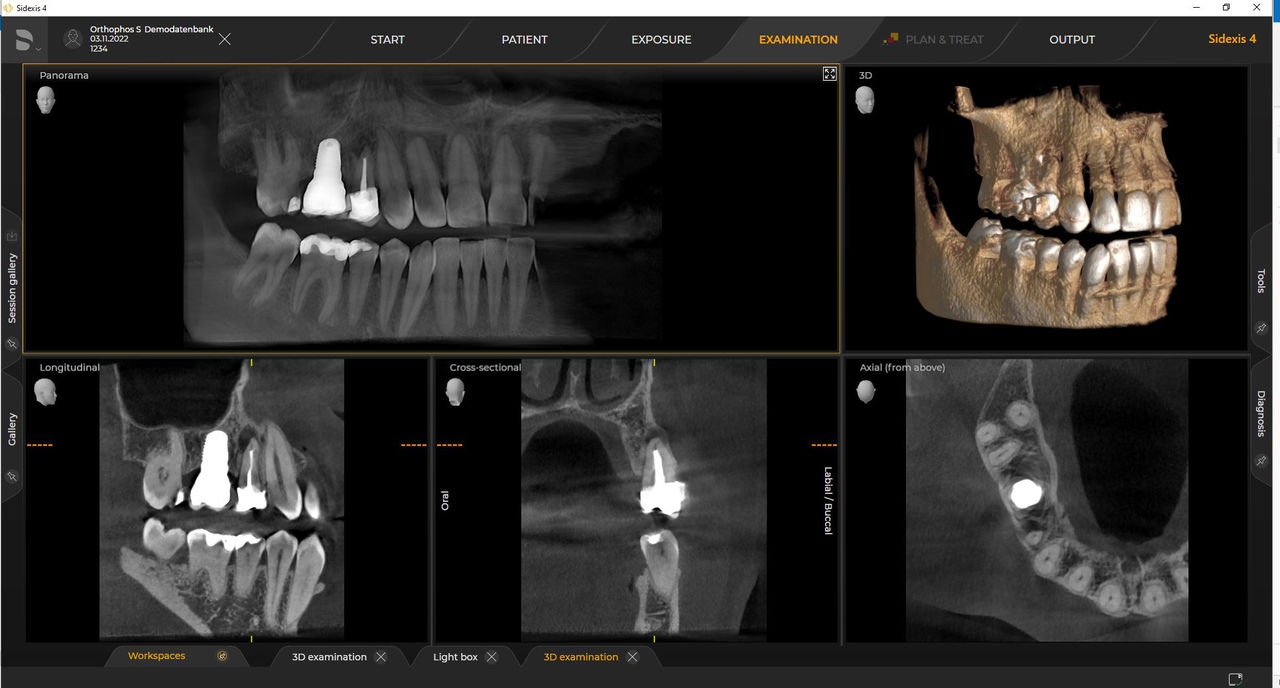

Las unidades de radiología de Dentsply Sirona funcionan exclusivamente con Sidexis 4. Sin embargo, la migración de datos de Sidexis XG a Sidexis 4 es muy fácil. Sidexis 4 permite una experiencia digital completa con las últimas herramientas

Con el modo de dosis baja inteligente 3D, obtiene imágenes 3D en el rango de dosis de una imagen radiológica 2D. En el modo HD (hasta 1400), las imágenes individuales se obtienen durante una única rotación y se convierten en un volumen 3D con hasta 80 μm para imágenes de bajo ruido en alta resolución.